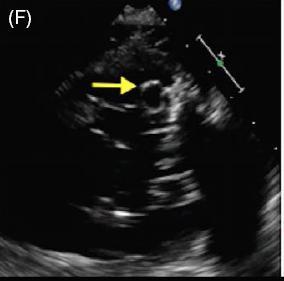

患者女,42 岁,以「急性视网膜动脉闭塞」病史就诊,既往无慢性疾病。经胸超声心动图检查发现二尖瓣后叶可见一囊状结构,可活动(图 A 和 B)。二维和实时三维经食管超声心动图检查显示一柔软的圆形结构附着于二尖瓣后叶,活动性良好(图 C ~ G)。主动脉弓、左心房、左心耳和左心室均正常。根据病变形态特征及超声表现,诊断为二尖瓣附瓣。其它影像学检查如 MRI、颈动脉多普勒超声均无异常。基于上述检查结果,考虑急性视网膜动脉闭塞为 AMVT 所致,建议外科手术切除二尖瓣附属组织,但是患者拒绝,选择随访观察。

图 C~F 二维经食管超声心动图显示一柔软的圆形结构附着于二尖瓣后叶,活动性良好